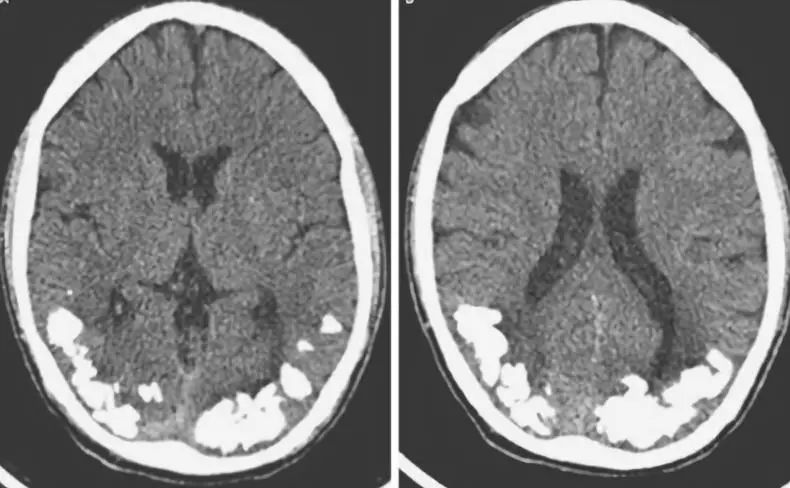

2. 假性甲状旁腺功能减退

疾病见下图。